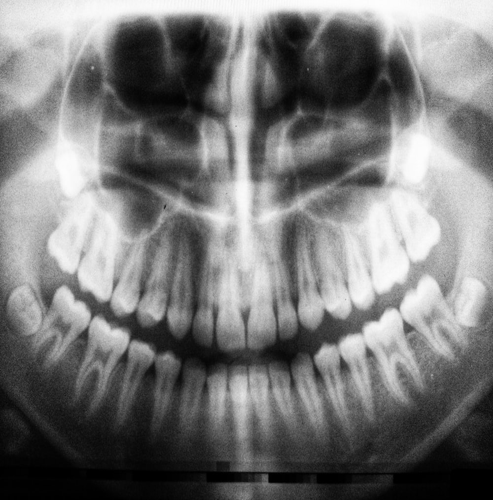

검진 과정에서는 치아의 발육 상태, 치아의 피해 여부, 구강 위생 상태 등을 종합적으로 평가합니다. 이를 통해 영유아의 구강 건강 상태를 파악하고, 필요한 치료나 예방 조치를 취할 수 있습니다. 영유아의 치과 검진은 꼭 전문적인 치과 전문의에게 맡기는 것이 좋습니다.

구강검진은 영유아의 구강건강을 평가하고 질환을 조기에 발견하며, 치아 건강을 유지하는 데 도움을 줍니다. 영유아의 구강건강을 관리하기 위해 국가건강검진에서 제공하는 구강검진을 이용하는 것이 좋습니다.